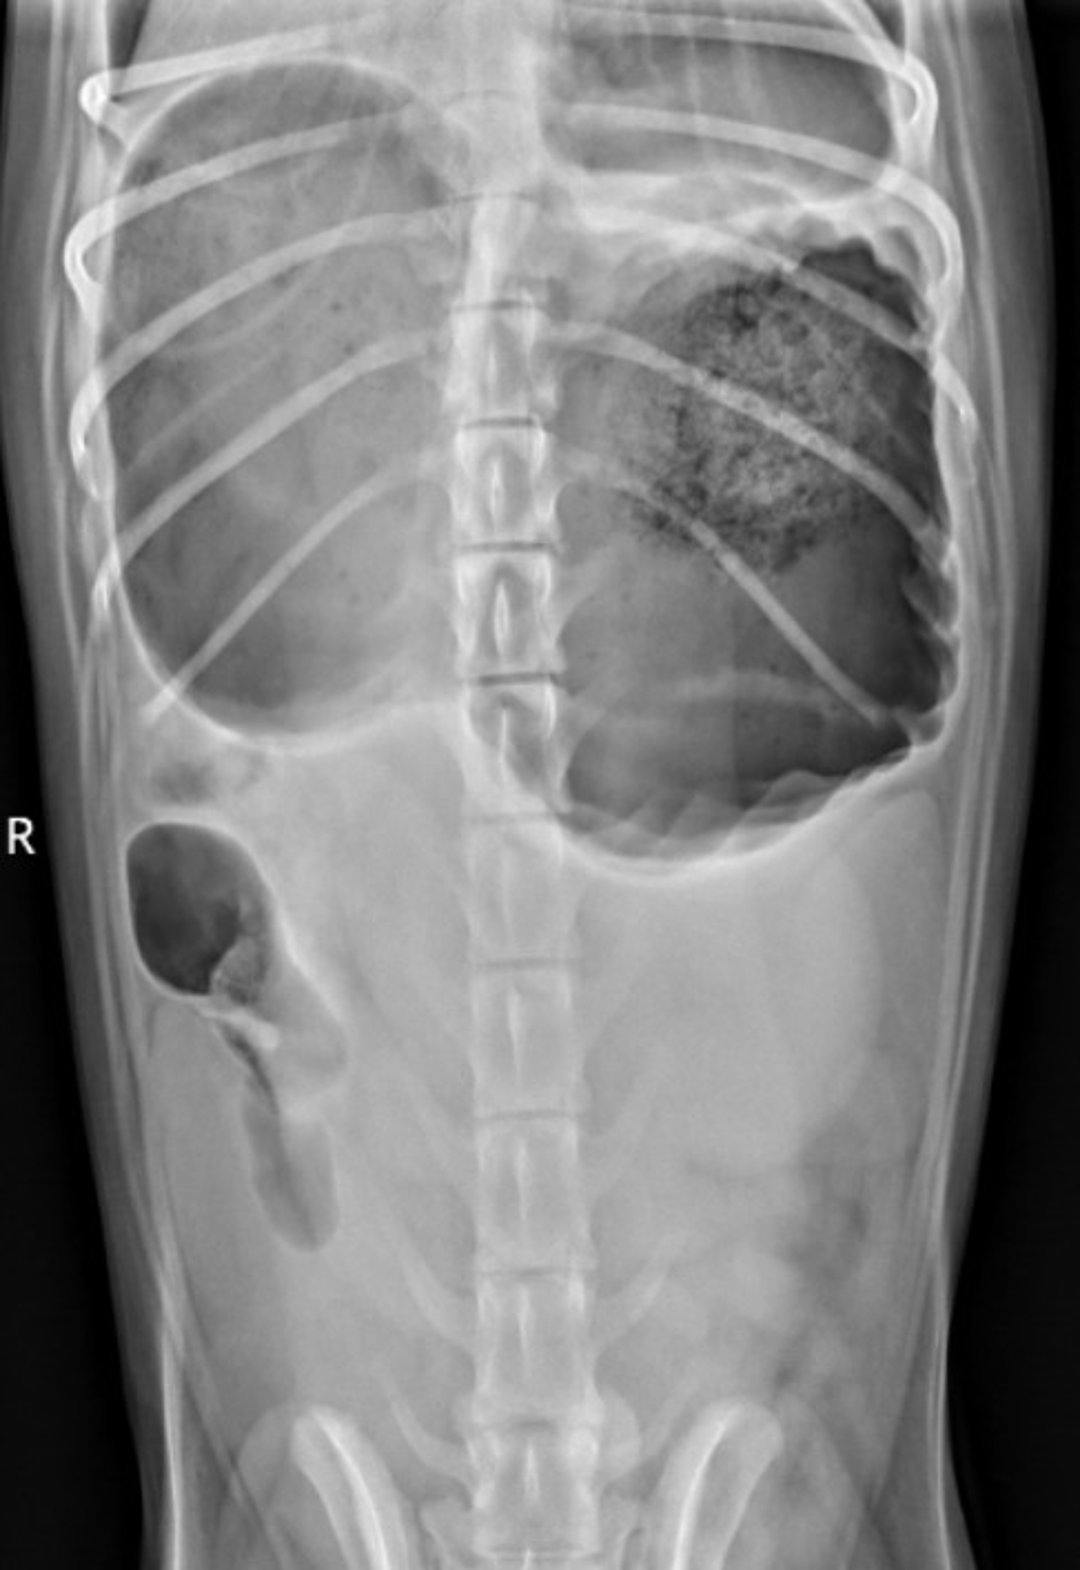

Ventrodorsal radiograph showing the "double bubble" in an 18-month-old Standard Poodle with gastric dilation and volvulus.